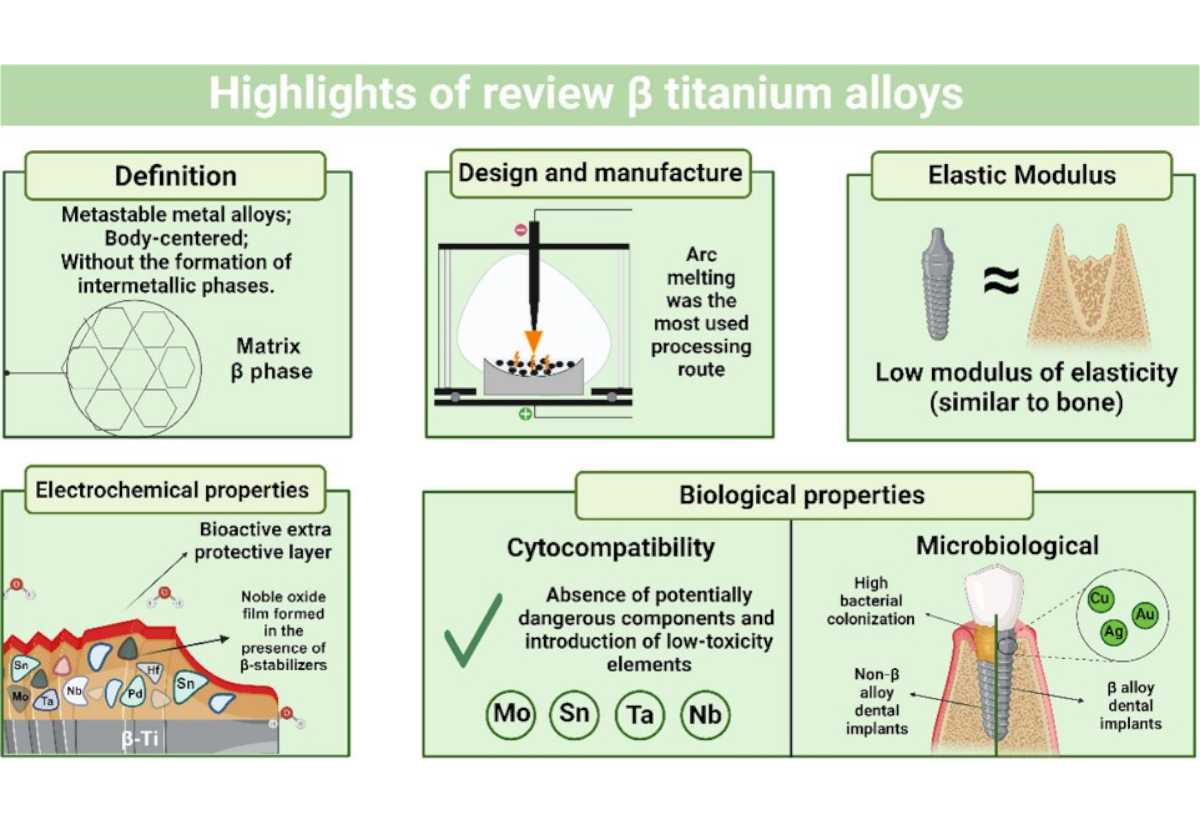

- 1 титановый имплантат